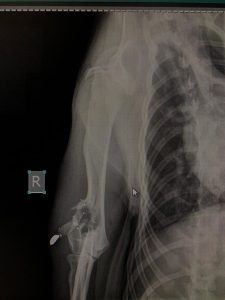

- Liječenje prijeloma kostiju, uključujući intraartikularne frakture

- Liječenje rupture prednjeg križnog ligamenta koljena TPLO (eng. Tibial Plateau Leveling Osteotomy)